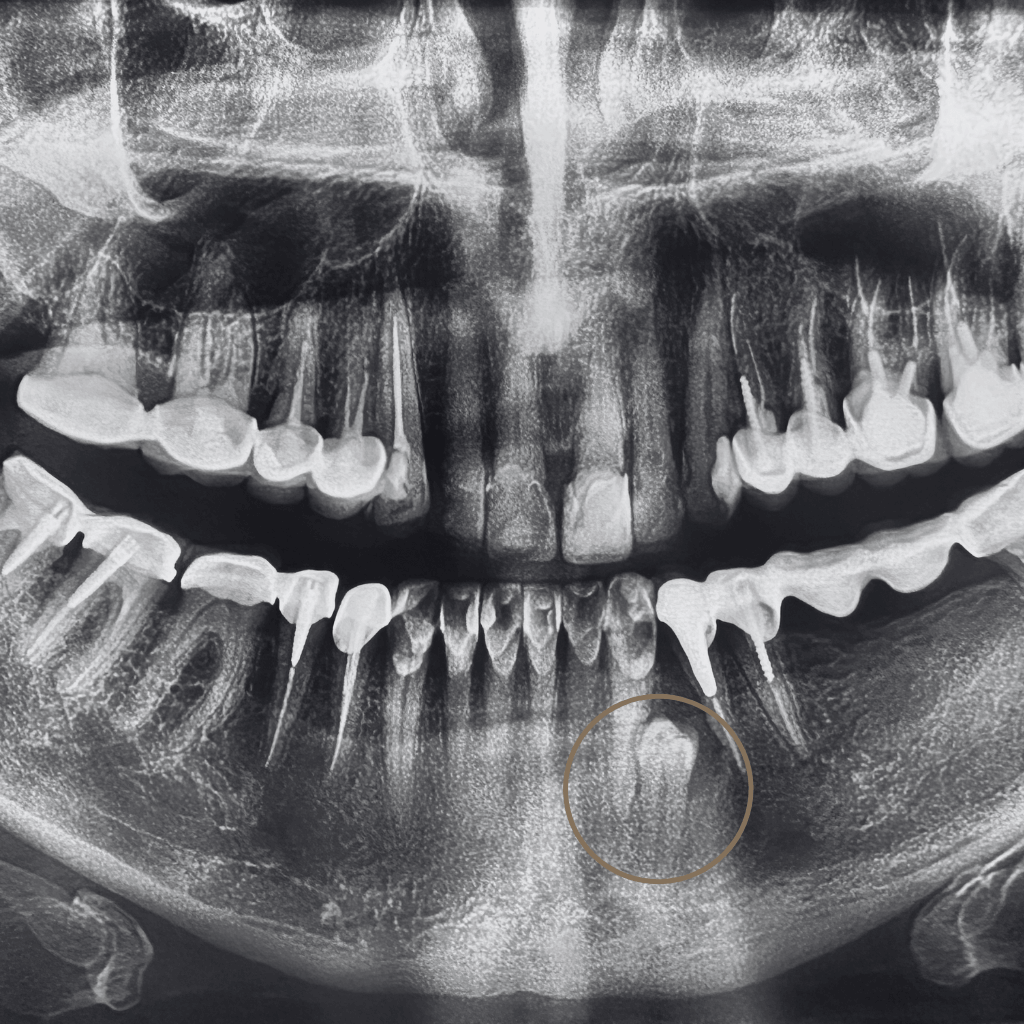

Зъб, който не е пробил напълно или е останал задържан в костта, се нарича ретиниран. Най-често това засяга мъдреците, но може да се отнася и за други зъби. В много случаи състоянието протича без симптоми, но може да доведе до болка, възпаление или увреждане на съседни зъби.

Когато ретинираният зъб създава или крие риск от възпаление, болка, увреждане на съседни зъби или затруднява хигиената в зоната, хирургичната намеса е препоръчителна. Най-често това се отнася за мъдреците, но ретенция може да се наблюдава и при други зъби, като кучешки или премолари.

В някои случаи ретинираният зъб може да остане безсимптомен за дълъг период. В Aesthetico решението за хирургична екстракция се взема индивидуално, след внимателна оценка на позицията на зъба и потенциалните рискове, включително при по-сложни анатомични ситуации.